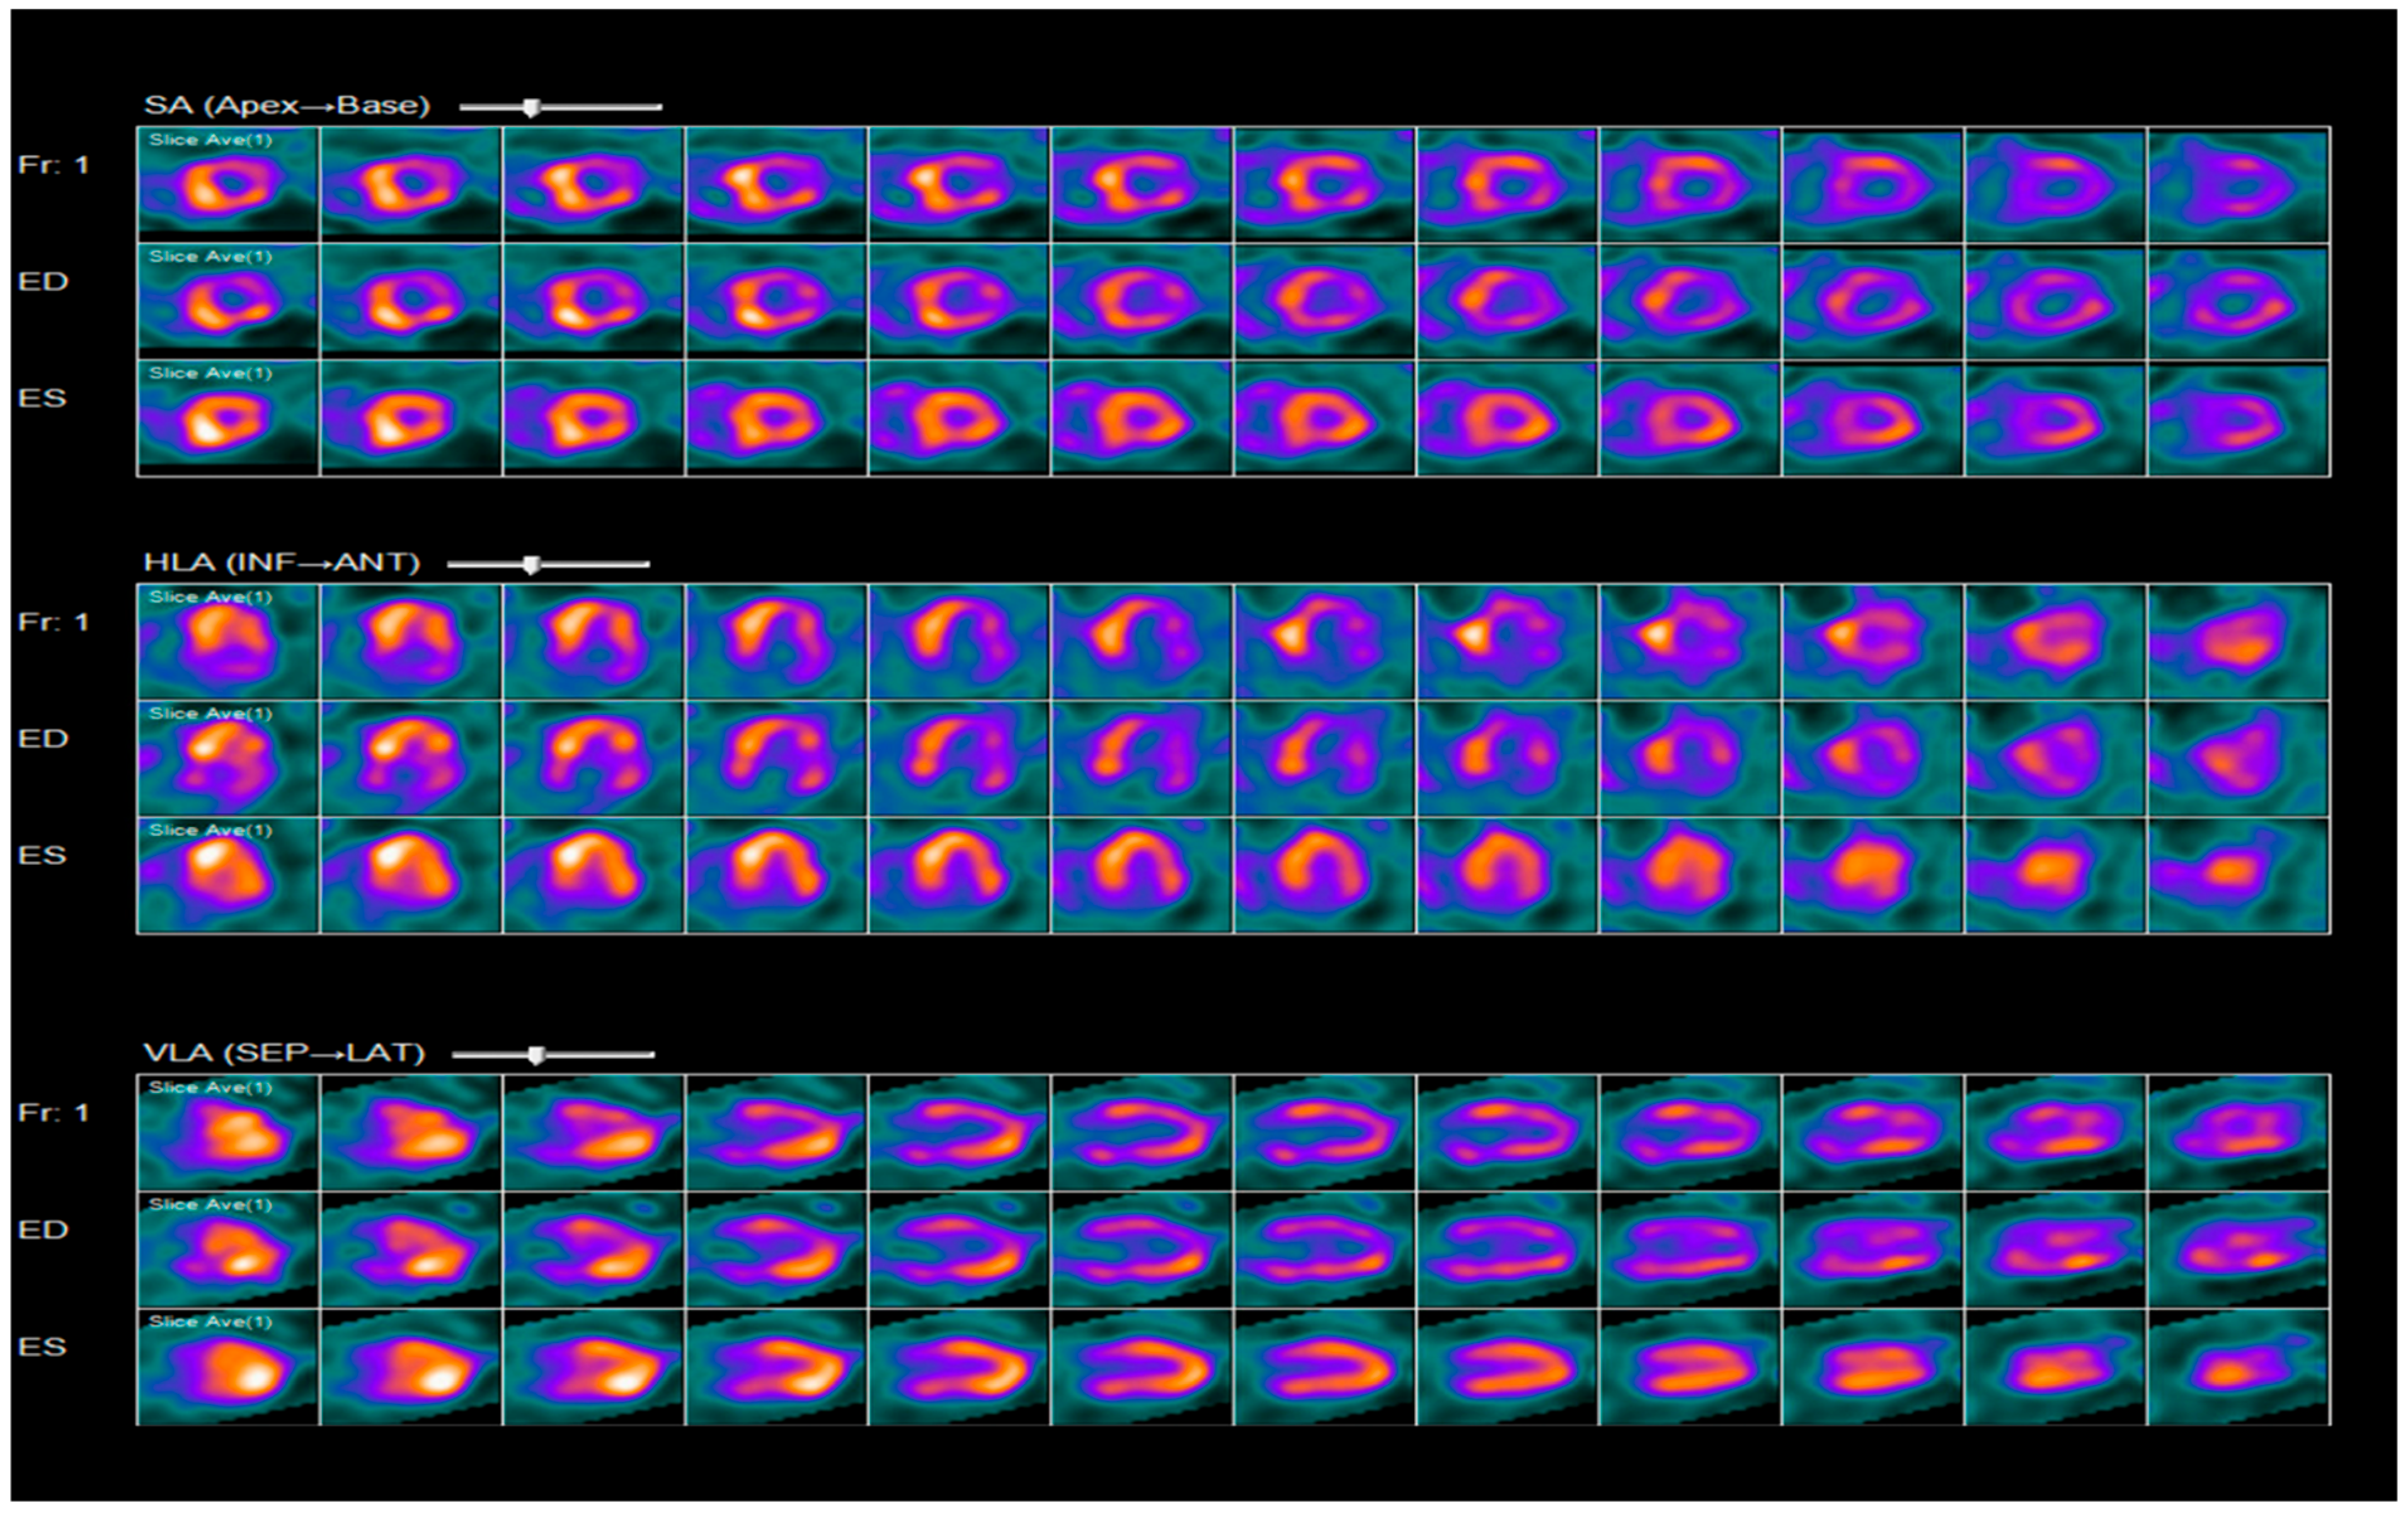

2.3. Diagnosis